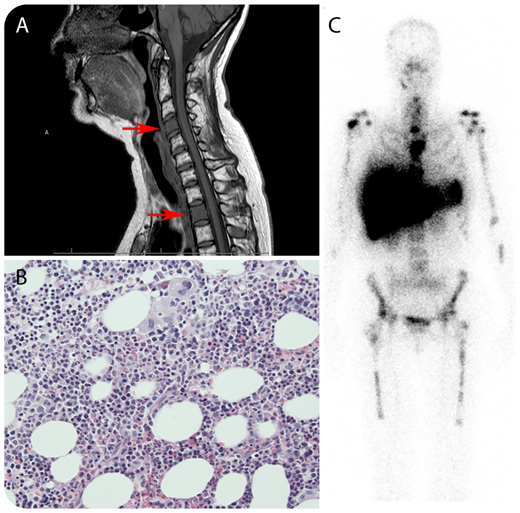

A 47-year-old woman presented with complaints of severe, persistent neck pain, 7 years after treatment of severe aplastic anemia with immunosuppression (antithymocyte globulin, methylprednisolone, and cyclosporine). A complete remission was achieved 5 months after this treatment. When her complaints were analyzed with a magnetic resonance imaging (MRI) scan of the cervical spine, an image suspicious for metastases in several vertebral corpora was found (panel A, MRI of the cervical spine; arrows indicate aberrant signals of the corpus of cervical vertebra 4 and thoracic vertebra 2). An 18F-fluorodeoxyglucose positron emission tomography (18F-FDG-PET) computed tomography (CT) scan revealed FDG-avid lesions throughout the axial spine, sternum, sacrum, femurs, and both mammae. Biopsies were taken from the mammary lesions, showing no malignancy. Subsequently, biopsies were taken from the right femur and sacrum, showing normal hematopoiesis without suspicion for malignancy (panel B; original magnification ×20, hematoxylin and eosin stain). Next, bone-marrow (BM) scintigraphy (99mTc-nanocolloid) was performed, confirming focal spots of increased BM activity in the suspected lesions (panel C). Here, increased and patchy BM activity may have been caused by patchy BM reconstitution in response to treatment in the setting of aplastic anemia. On MRI or 18F-FDG-PET/CT scan, increased BM activity may mimic malignant disease. BM scintigraphy using 99mTc-nanocolloid is preferred over 18F-FDG-PET or 18F-fluorothymidine–PET scan to demonstrate this, because it differentiates between hematopoiesis and other tissues.

Clinically, the neck pain resolved spontaneously and was probably unrelated to BM activity because the patient had no pain at other involved sites.